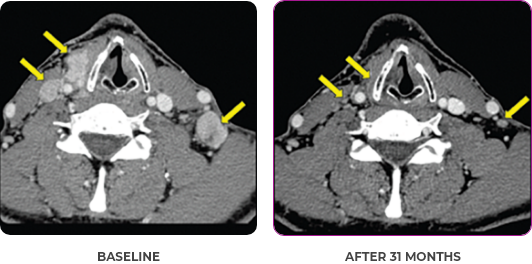

BASELINE

AFTER 31 MONTHS

33-YEAR-OLD MALE4

PATIENT CASE:

METASTATIC, RAIa-REFRACTORY,

PAPILLARY THYROID CANCER1,2

- 33-year-old male

- Progression on RAI and first line systemic therapy

- PRa after 2 cycles of VITRAKVI® (larotrectinib)

- Confirmed partial response on VITRAKVI lasting 55 cycles

Clinical presentation1

- Initially diagnosed at age 27

- Bulky disease in neck and thoracic involvement; metastatic, RAI-refractory papillary thyroid cancer

VITRAKVI treatment1

- VITRAKVI 100 mg twice daily orally

Response to VITRAKVI1,2

- Confirmed partial response (92.6% reduction in target lesions)

- Treatment continued for 55 cycles

- VITRAKVI was well tolerated; patient did not have to discontinue due to AEa

- No treatment interruptions or dose reductions

Response in primary and metastatic lesions1

Images courtesy of Dr Steven Waguespack.